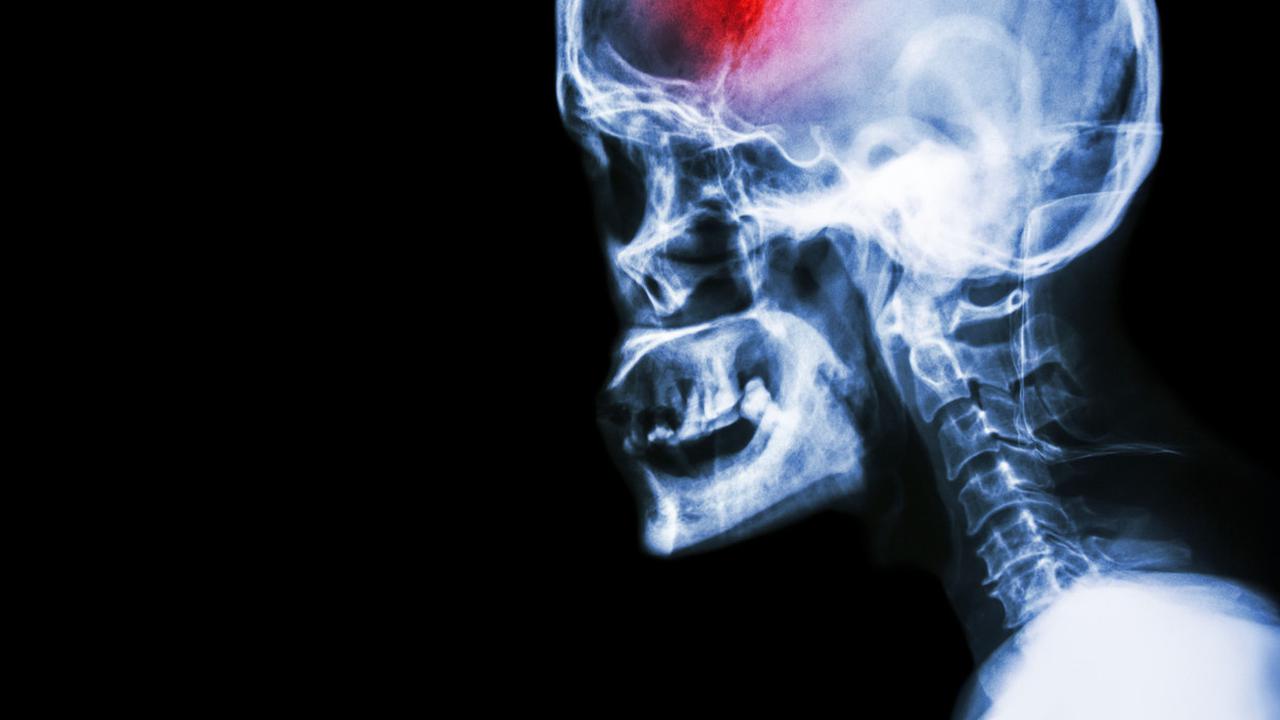

Liputan6.com, Jakarta Terapi kejut listrik untuk mengatasi stroke kini hangat diperbincangkan setelah sebuah video yang memperlihatkan pasien stroke diterapi oleh seseorang berseragam TNI cukup viral. Dalam video, terapi alternatif itu dilakukan menggunakan kabel, colokan, serta lempengan.

Tujuan dari terapi kejut listrik agar saraf yang tersumbat dari pasien stroke dihidupkan kembali. Aliran darah pun kembali lancar.